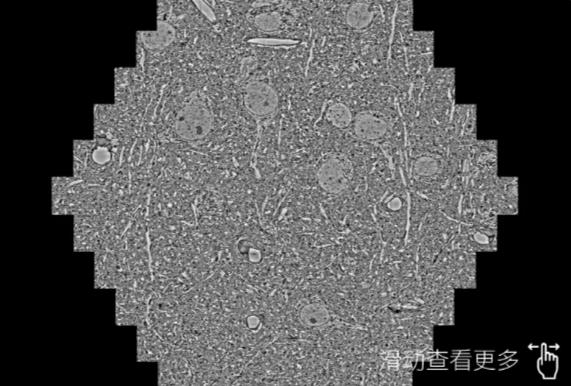

鼠脑切片。左图使用随州蔡司随州扫描电镜MultiSEM706对165μmx143pm面积区域成像,耗时仅需1.5秒。右图为鼠脑切片中30μm区域放大效果。样品由芝加哥大学B.Kasthuri提供。

使用蔡司高速随州扫描电镜MultiSEM对1mm²人脑皮层组织进行高分辨成像,并对其中的各种细胞结构进行三维重构分析。左图展示了2x3mm²组织平面中锥体神经元的三维重构效果。右图显示了局部体积神经元三维重构。图像由哈佛大学chtman实验室提供,渲染图由D. Berger 制作。